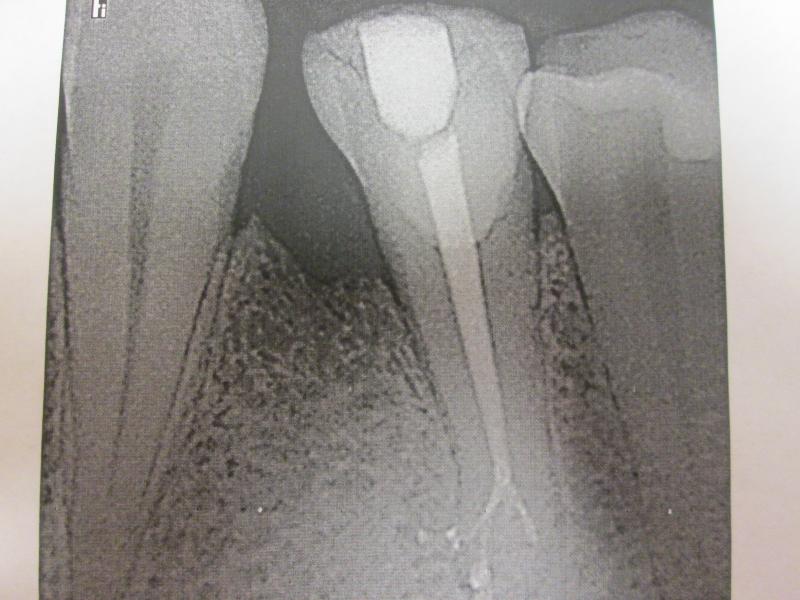

DR JET LOVES ROOT CANALS

General Dentist,  Performs Root Canals ONLY - Microscope Trained Dentist

"DR. JET'S MISSION IS TO PERFORM  ROOT CANALS FOR A REDUCED FEE USING THE LATEST TECHNOLOGY  AND TECHNIQUES TO SERVICE THE MANY PEOPLE WHO ARE UNINSURED OR UNDER-INSURED GIVING EVERYONE AN OPPORTUNITY TO SAVE THEIR TOOTH!"